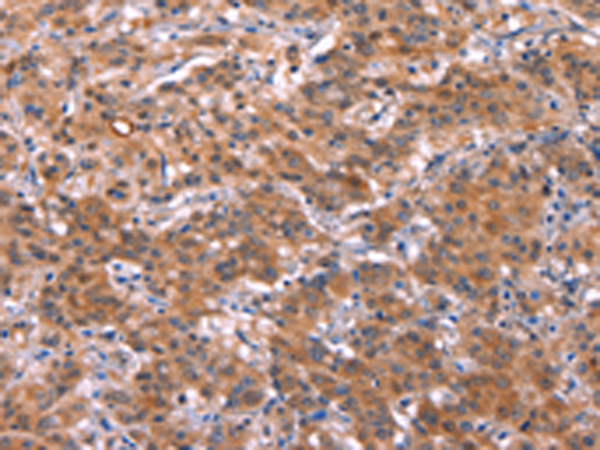

分类: 科研抗体货号: P04922别名: PBF; PRF1; HDBP2; PRF-1; HDBP-2; HDRF-2; Si-1-8-14应用: IHC反应种属: Human